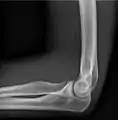

AP and lateral elbow X-ray

• Elbow - AP and Lateral. Radial head projections available on request